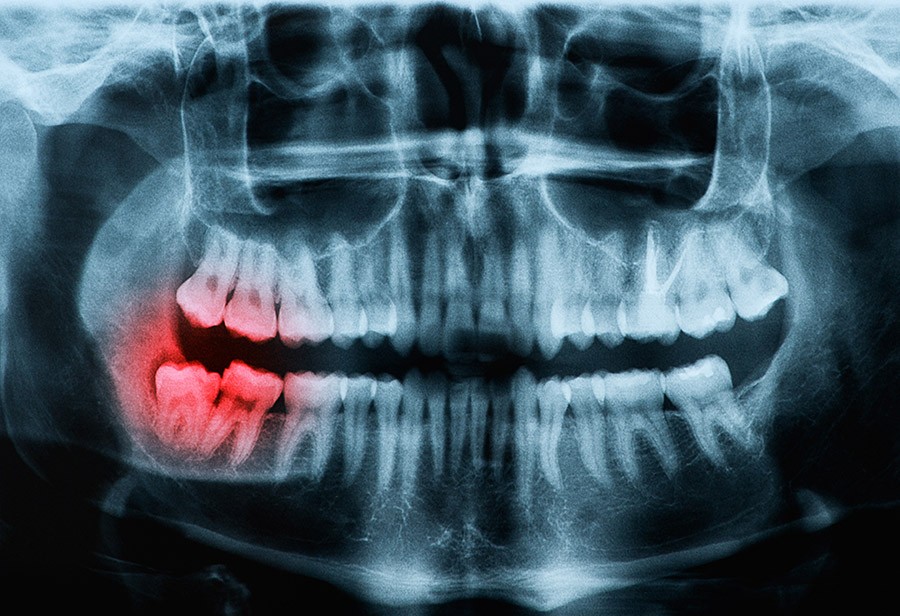

- Early detection of dental issues

- Treatment for cavities and other dental problems

Your mouth naturally creates a film over your teeth that becomes plaque. Plaque can harden into tartar, and tartar can lead to tooth decay and gum disease. By brushing your teeth twice a day and flossing once a day, you break the film before it can become tartar. When you visit us for regular teeth cleanings, we’ll remove tartar from any spots you missed. We can also coat your teeth with fluoride to toughen your enamel and fight tooth decay.